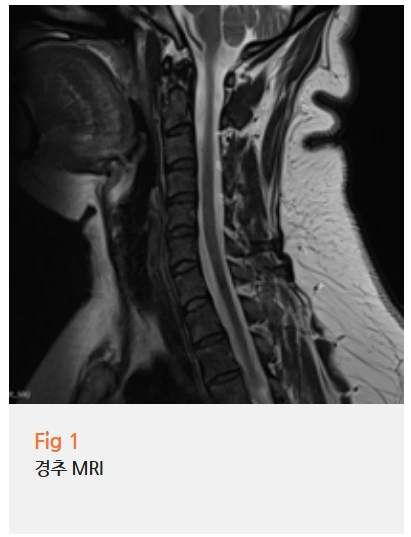

그래서 당일 MRI 촬영을 진행했죠.

MRI 검사 결과는 예상을 확인시켜줬습니다.

경추에서 경미한 추간판 변성이 발견됐고,

이로 인해 신경근이 자극받고 있었던 거예요.

특히 C5-C6, C6-C7 부위의 신경근이 자극받으면

겨드랑이 부위로 방사통이 나타나는 경우가 많습니다.

이 환자분도 정확히 그런 케이스였어요.